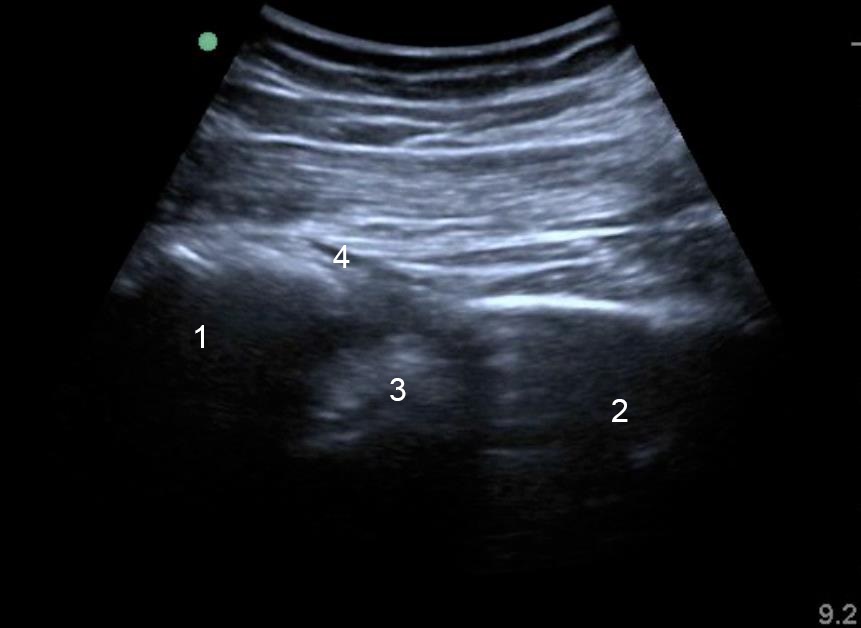

Imagen 2 de la estructura ósea de la parte posterior de la cadera

1. Sacro

2. Isquion

3. Agujero o foramen ciático mayor

4. Arteria glútea superior